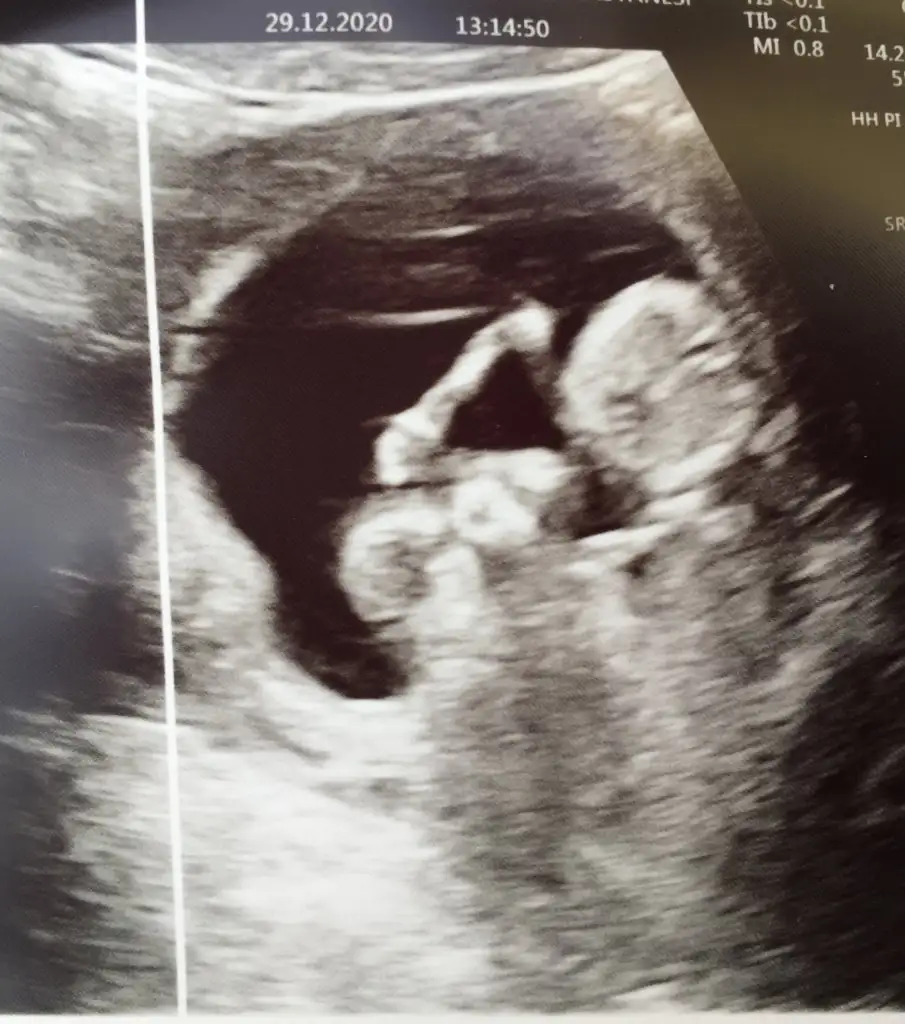

Diğeride emin değildim bu usgde 16 hafta nub olmaz artık16 haftalik cinsiyet tahmininiz nedirIkra meyra ?

Öğrendik canım evet Dr %100 erkek dedi 2. Kez oğlum olacak, çok teşekkür ederim sanadaDiğeride emin değildim bu usgde 16 hafta nub olmaz artıkgörünen pipi ise sanki erkek belkide değildir 16 haftadan pek anlamıyorum cnm gönlünüzden geçeni nasip etsin rabbim inşallah ogrenmedinizmi

Pipimi bu yoksa kordonmu emin olamadım ogrendik